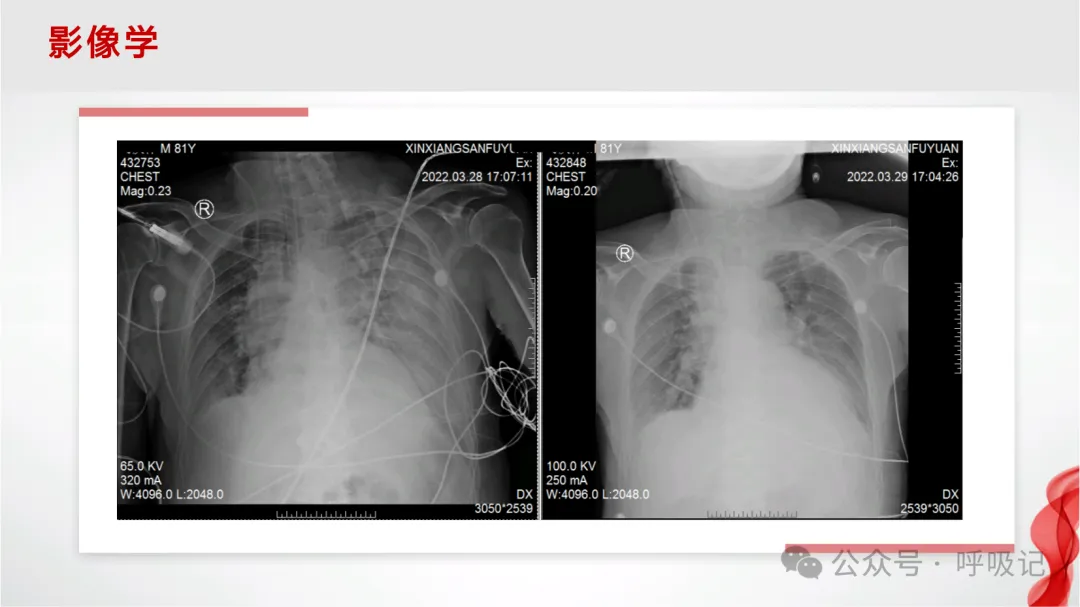

>AECOPD机械通气【PPT】

AECOPD机械通气【PPT】